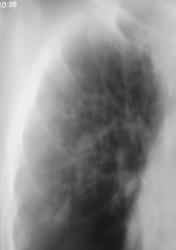

Иллюстрации 3, 4. Справа определяется почти диффузное усиление, обогащение и деформация легочного рисунка, на фоне чего дифференцируются очаговоподобные тени, округлые мелкие просветления. Тень правого корня полностью нивелирована, смещенным вправо средостением.